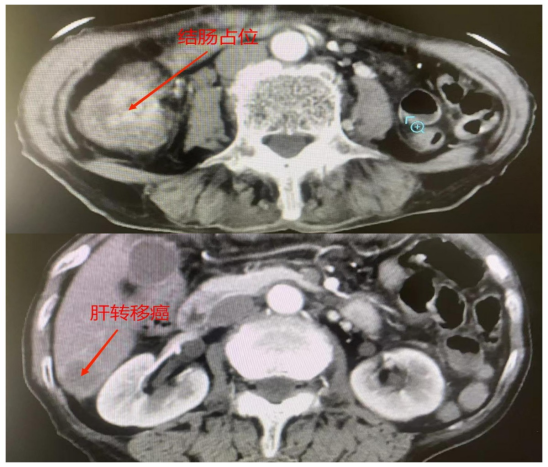

但是近1月以来,徐奶奶的腹痛、腹胀越来越严重,于是在家人的陪同下她来到深圳恒生医院希望得到进一步治疗。入住消化内科后医生给她做了肠镜+CT检查,发现患者不仅结肠癌已经到了晚期,还出现肝脏转移瘤。征得患者及家属同意后,转普外科手术治疗。

(患者CT情况)

“结肠癌因为它发展的特点,非常容易出现肝转移,而肝转移正是结肠癌患者最常见的死因。” 普外科程明主任介绍道。